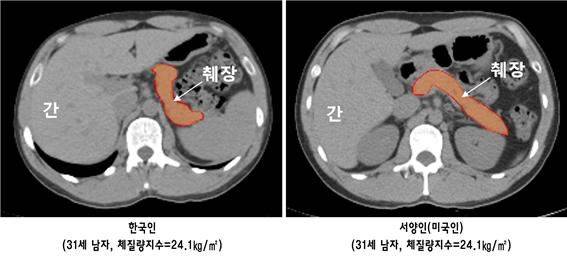

임수 분당서울대병원 내분비내과 임수 교수팀은 최첨단의 컴퓨터 단층촬영(CT)을 통해 체격이 유사한 30대 연령의 한국인과 서양인 각 43명의 췌장 용적(볼륨) 및 췌장 내 지방 함량을 비교했다. 이와 함께 췌장 베타세포에서의 인슐린 분비능과 당대사능을 측정해 췌장의 크기 및 지방함량과 인슐린 분비능 사이의 관련성을 분석했다.

하지만 췌장 크기에서 차이를 보였다. 연구팀이 췌장 용적을 비교한 결과, 한국인은 서양인에 비해 췌장의 크기가 12.3% 정도 작았지만 췌장 내 침착된 지방의 양은 서양인에 비해 22.8% 더 많은 것으로 확인됐다. 췌장 내 침착된 지방이 많으면 지방세포에서 분비하는 염증유발 물질 사이토카인, 혈관활성화 물질 등이 베타세포를 감소시키고 췌장의 기능저하를 일으키는 것으로 알려져 있다.